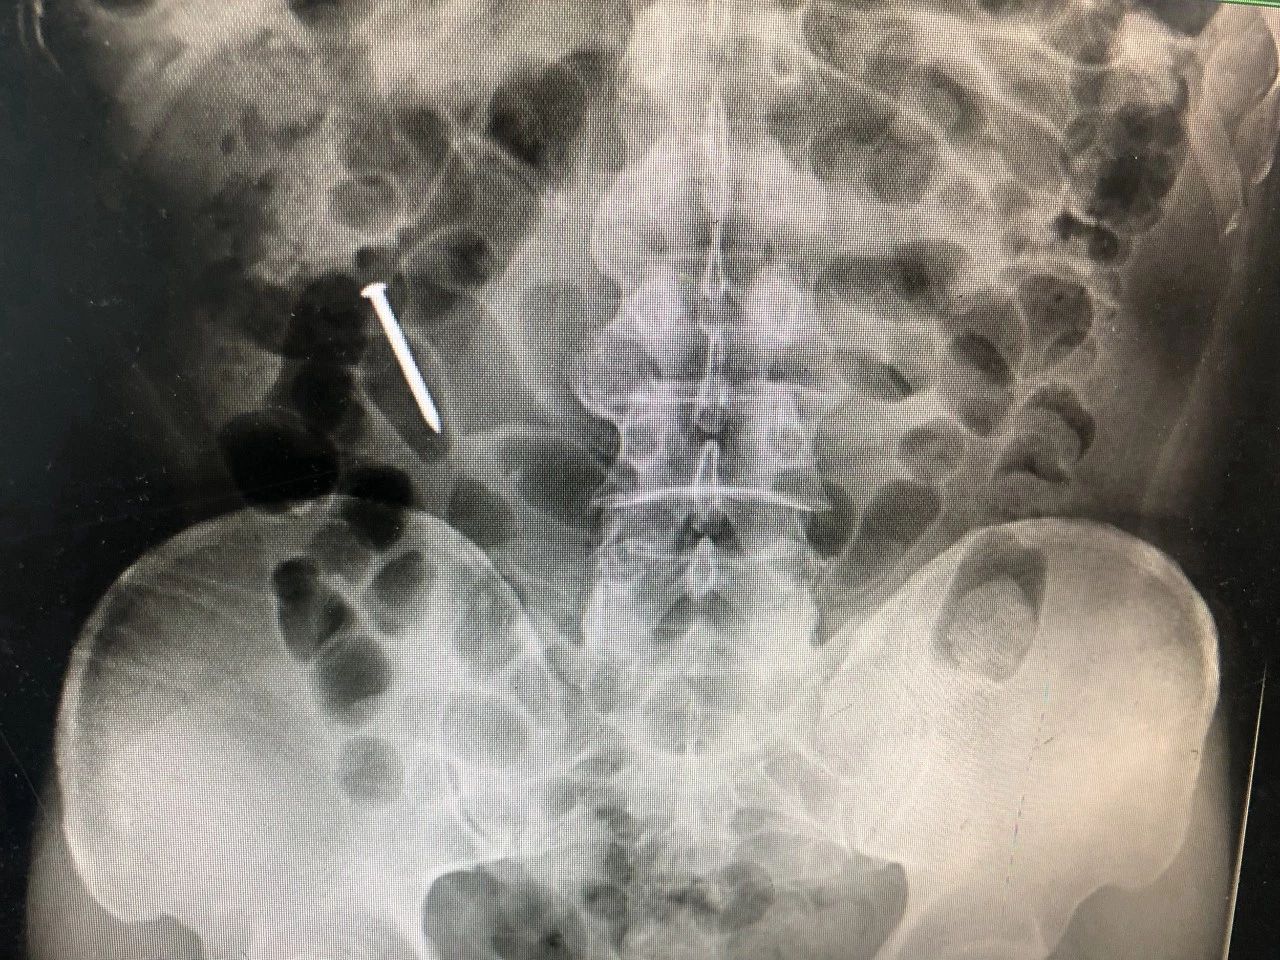

腹部X片检查

发现钉子,但不能确定具体位置

CT检查

在罗锋空肠中下段部位发现了钉子

由于钉子在罗锋肚子里“待”的时间较长,已经滑落到他的空肠中下段部位,目前无法用内镜直接将钉子取出。那该怎么办?